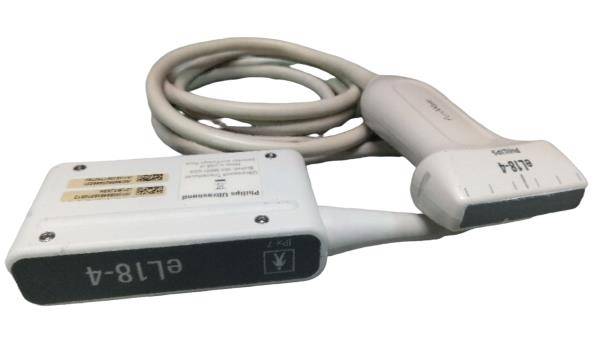

Sonde micro-convexe |

Abdominale linéaire |